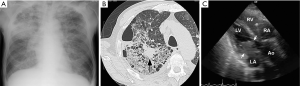

A 64-year-old male was admitted to the hospital because of dyspnea at rest and fever. He reported a history of 10-kg weight loss for six months, cough for two weeks, and fatigue, dysphagia and muscle weakness for one week. He smoked three packs of cigarettes per day for over 40 years. On admission, the height was 167 cm and the weight 55 kg, the blood pressure 97/70 mmHg, the pulse 115 beats per minute, the temperature 37.1 degree C and SpO2 92%. Chest radiograph showed pulmonary congestion and opacity in the right upper lung (Figure 1A). Chest CT scan revealed opacity in the right upper lung with a tumor of approximately two cm in diameter in it (Figure 1B). Electrocardiogram showed no specific abnormality. Treatment with antibiotics and oxygen were started but his condition and respiration was progressively worsened next four days. Echocardiogram on third hospital day showed a large mass in the left atrium that caused obstruction of the mitral inflow of left ventricle (Figure 1C). Surgical removal of the mass was not selected because of his condition. He died of cardiac inflow obstruction four days after the admission. An autopsy was performed.